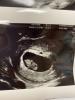

Была на УЗИ)) сердечко бьётся)))

Срок 7.1 недель, поздняя овуляция)

@solnce66 9.5)